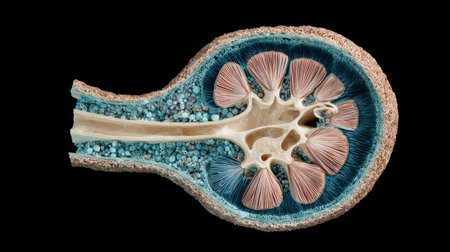

Anatomical image of the human kidney in cross section. disorders of kidney physiology,

A stunning cross-sectional illustration of a fruit revealing vibrant colors and intricate internal structures, perfect for educational and artistic purposes.

Human kidney cross section on science background. 3d render

Human kidney cross section on scientific background. 3d illustration